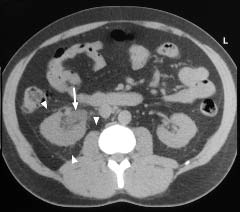

CT IVU through the renal area. The right renal pelvis is mildly dilated (arrow) and a small amount of perirenal stranding is noted, suggestive of obstruction

(arrowheads).